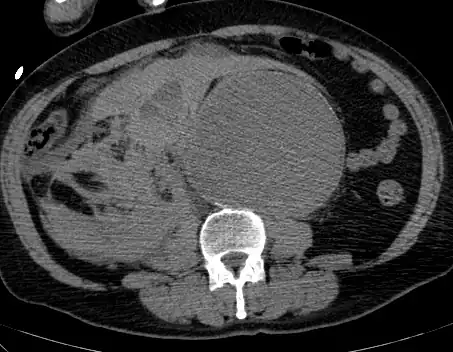

The diagnosis of an abdominal aortic aneurysm can be confirmed by the use of ultrasound. Rupture may be indicated by the presence of free fluid in the abdomen. A contrast-enhanced abdominal CT scan is the best test to diagnose an AAA and guide treatment options.[10]